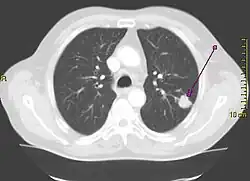

Le cancer du poumon peut être vu sur les radiographies thoraciques et le scanner. Le diagnostic est confirmé par une biopsie. Ceci se fait généralement par bronchoscopie, ou par biopsie guidée par scanner. Le traitement et le pronostic dépendent du type histologique du cancer, de son stade (degré de dissémination), et de l'état général de santé du patient.

La radiographie thoracique est la première mesure à prendre si un patient se plaint de symptômes pouvant suggérer un cancer du poumon. Ceci peut révéler une masse évidente, un élargissement du médiastin (qui suggère une extension aux ganglions lymphatiques qui s'y trouvent), une atélectasie (affaissement), une inflammation (pneumonie) ou un épanchement pleural. En l'absence de signes radiographiques, mais si les soupçons sont élevés (par exemple, un gros fumeur avec hémoptysie), une bronchoscopie ou un scanner peuvent donner l'information nécessaire. La bronchoscopie ou la biopsie guidée par scanner sont souvent utilisées pour identifier le type de tumeur[3].